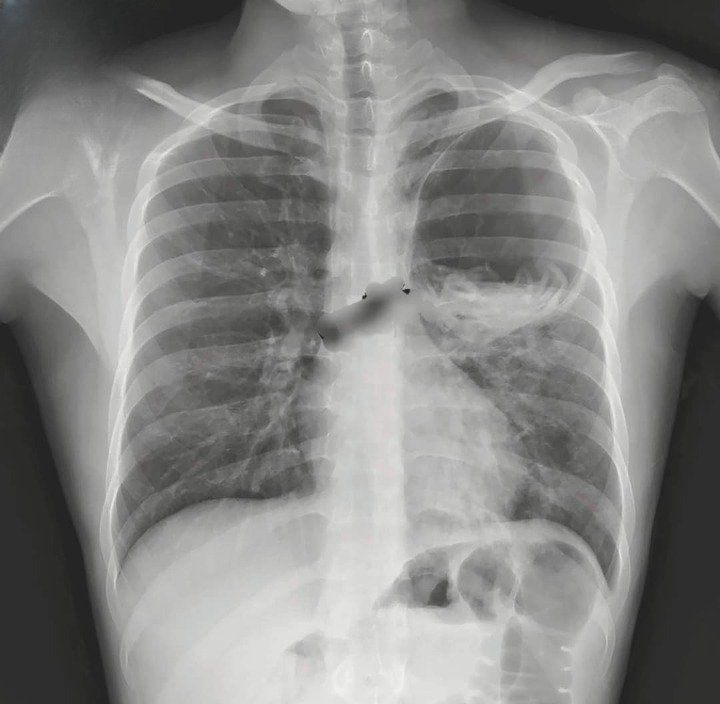

مريض عمره 35 سنة

يعاني مني سعال + بلغم + دم Hemoptysis

ما التشخيص المحتمل انطلاقا من الصورة المميزة 🪷؟